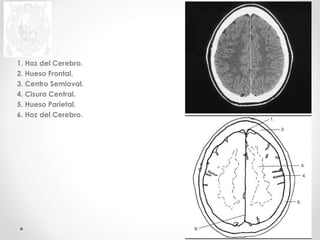

1. Hoz del Cerebro.

2. Hueso Frontal,

3. Centro Semioval.

4. Cisura Central.

5. Hueso Parietal.

6. Hoz del Cerebro.

2. Hueso Frontal.